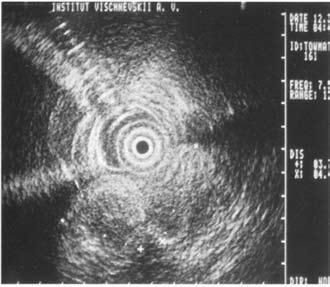

Достаточно достоверные данные о местном распространении опухоли, инвазии сосудов, регионарных метастазах могут быть получены при использовании эндоультрасонографии (ЭУСГ) – нового метода диагностики, эффективность которого широко обсуждается в литературе. При этом исследовании датчик можно подвести непосредственно к опухоли (лапароскопически, через желудок и ДПК, интрадуктально через БДС, интрапортально), что позволяет выявить образования менее 1 см, а при интрадуктальном УЗИ – опухоли до 2 мм, увеличенные лимфатические узлы, инвазию крупных сосудов, выполнить игловую биопсию этих образований. Недостатком ЭУСГ является большая зависимость результатов исследований от опыта врача, выполняющего исследование, что существенно ограничивает его применение и мешает широкому распространению метода (рис. 102).

Рис. 102. Эндоскопическое УЗИ. 1. Опухоль головки ПЖ. 2. Расширенный терминальный отдел общего желчного протока